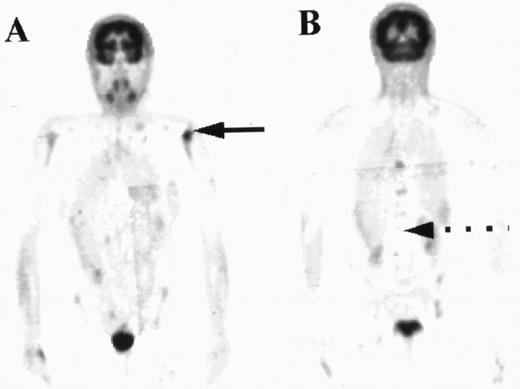

The distribution of uptake within the marrow was noted. Focal abnormality is seen within the lumbar spine in patient A (arrow), while patient B has diffuse marrow abnormalities.